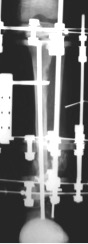

Alınan periost KTP sahasına sirküler olarak sarılır. (Cambium tabakası kemiğe doğru dönük olmalıdır). Araya alınan kortiko-spongiöz greftler yerleştirilerek periost greftinin iki ucu absorbe olan sutur materyeli ile birleştirilmelidir.

Hemostazı takiben katlar anatomik olarak kapatılmalıdır. Daha önceden hazırlanmış 3 halkadan oluşan sirküler eksternal fiksatör K-telleri ile frontal ve sagittal planlarda anatomik eksene paralel olarak yerleştirilmelidir. Burada dikkat edilmesi gereken fiksatörün K-telleri ile Steinmann çivisi temas etmemelidir. Proksimal tibia’dan fizise çok yakın kortikotomi ile mevcut kısalık da rekonstrukte edilir.

Bu tekniğin amacı hastada mevcut olan psödartroz, kısalık ve deformiteden oluşan tüm patolojilerin tek bir ameliyat ile giderilebilmesidir. Böylece postoperatif refraktür, kısalık, fibular psödartroz tek bir cerrahi girişimle tedavi edilebilir. Hastalar birer aylık aralıklarla diz ve ayak bileği ROM, ağrı, çivi dibi enfeksiyonu, yeni oluşan rejeneratın kalitesi gibi klinik kriterler açısından değerlendirilir. Radyolojik olarak da MPTA ( medial proksimal tibial açı), LDTA (lateral distal tibial açı),kısalık farkı, İM çivinin migrasyonu tetkik edilmesi gereken başlıca kriterlerdir.